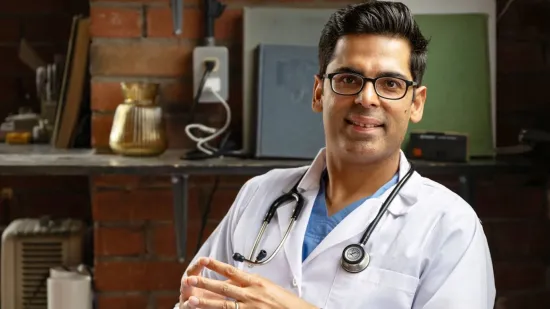

Dr. Zachary Palace, medicinski je direktor Hebrejskog doma u Riverdaleu u New Yorku koji tvrdi da je otkrio strategiju koja bi osobu spasiti tik prije samog nastupanja kliničke smrti.

Liječnik tvrdi da bi uranjanje osobe u hladno okruženje moglo odgoditi sami proces, dajući liječnicima više vremena da je reanimiraju.

Inače, taj je postupak poznat i pod nazivom "terapeutska hipotermija", a koristi se kada pacijent ima srčani zastoj.

"Kada je osoba blizu smrti, postoje dvije faze kroz koje prolazi", rekao je dr. Zachary Palace.

"Prvo, tijelo doživljava ono što je poznato kao klinička smrt. Klinička smrt označuje nepovratan i konačan prekid srčanoga rada i krvnog optoka te disanja.

Oko šest minuta kasnije nastupa faza biološke smrti. Tada počinju odumirati i moždane stanice.

Dr. Palace otkrio je da bi uranjanje osobe u hladno okruženje moglo odgoditi biološku smrt.

Objasnio je: "Što je tijelo hladnije, metabolizam je sporiji, pa kisik sporije troše".

To znači da hlađenjem osobe ostaje više vremena liječnicima da pokušaju sve kako bi je vratili u život.